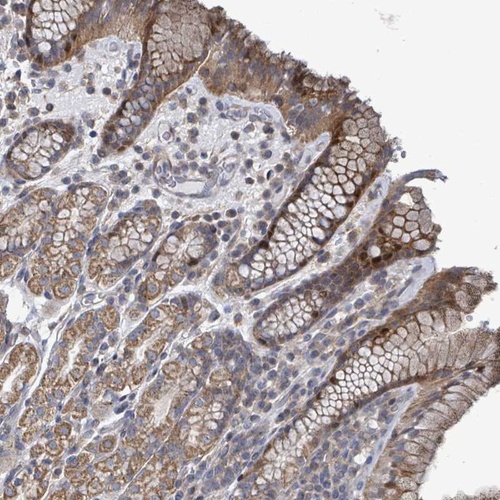

Immunohistochemical staining of human stomach, upper shows moderate cytoplasmic and nuclear positivity in glandular cells.